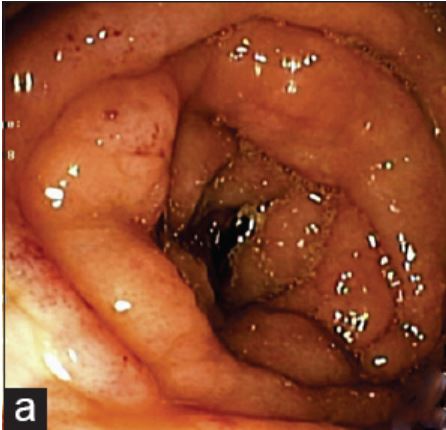

リンパ管腫と誤診される危険のある上行の濾胞性リンパ腫。鉗子で押すと柔らかい、との記載有り。

岡山大学 高嶋先生の論文より引用させていただきました